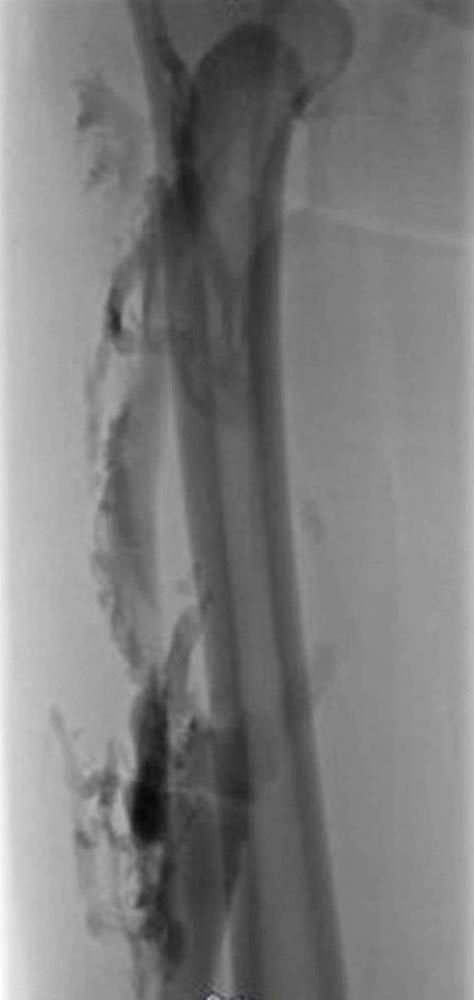

Phlebography has been almost entirely replaced by ultrasound, CT or MR phlebography for the diagnosis of phlebothrombosis and is no longer indicated. Phlebography nowadays is mostly performed as varicography in the direct puncture technique in the context of interventional procedures. In this situation the thrombus is visualized as an intraluminal contrast medium filling defect in the vein.

Invasive measures today often include minimally invasive, catheter-guided mechanical or pharmacomechanical procedures. In these procedures, the acute thrombus is dissolved by mechanical or pharmacomechanical catheter therapy in a minimally invasive manner. Chronic occlusion, especially in the iliofemoral location descending from an iliac vein, can also be reopened minimally invasively, and stents are usually implanted. Open surgical therapy of acute thrombosis is very rarely indicated today, primarily in cases of iliofemoral thrombosis with occlusion of the pelvic venous circulation, and may be combined with creation of an arteriovenous fistula in the groin to keep the reopened vein open. However, appropriate measures should always be performed at a center.